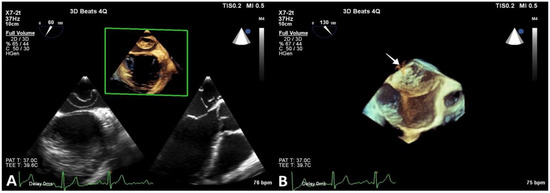

The patient denied having a family history of cardiovascular disease and symptoms of cardiac origin. She had an unremarkable medical history, and her physical examination was normal. Resting 12-lead electrocardiogram showed sinus rhythm with normal heart rate and no morphological anomalies. As part of the diagnostic work-up, transthoracic echocardiography was also carried out, revealing normal cardiac chamber size, left and right ventricular function, and no valvular heart disease. An echodense structure was identified bisecting the LA horizontally into postero-superior and antero-inferior parts. No significant pressure gradient was detected using continuous Doppler across the flexible membrane in the four-chamber view (Figure 2).

Figure 2.

Transthoracic echocardiography revealing CTS. (A) Parasternal long-axis 2D view showing an echodense, membranous structure within the LA (arrow). (B) Apical four-chamber 2D view showing the membrane bisecting the LA (arrow). (C) Apical four-chamber 2D view and color Doppler window placed over the LA, highlighting turbulent flow across the membrane (arrow).